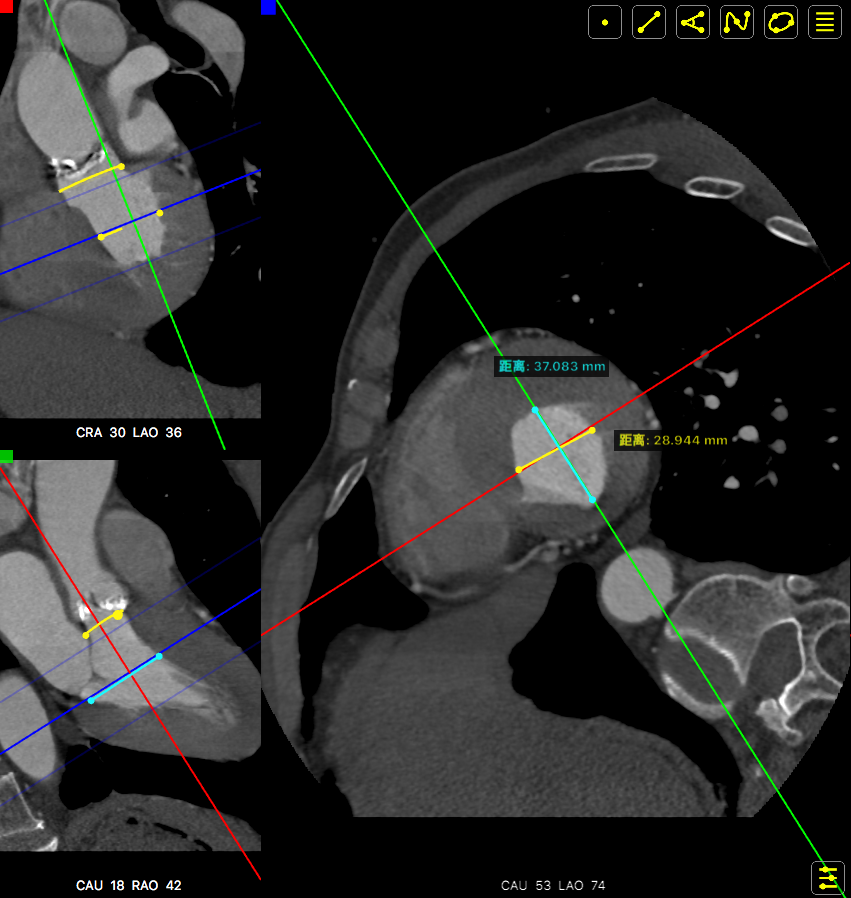

主动脉根部数据:

主动脉瓣环周长82.2mm(平均直径26.1mm),流出道周长89.6mm(平均直径28.5mm),左冠高度:15.4mm,右边冠高:14.9mm,主动脉窦宽28.7mm/33.7mm/34.9mm、STJ周长:93.5mm(平均直径29.7mm)高度22.2mm,升主动脉周长:111.7mm(平均直径35.5mm)。

术前心胸外科、心血管内科、超声科、麻醉科、体外循环、介入室等科室进行了术前讨论和术前策略分析:该患者主动脉瓣属于钙化狭窄的Type0型二叶瓣,左右冠脉同窦,无冠窦可见团状钙化,左右同窦钙化相对较少,主动脉瓣环周长82.2mm、呈现椭圆形,左室流出道周长89.6mm,主动脉窦宽28.7mm/33.7mm/34.9mm、窦宽可,STJ周长93.5mm、高度22.2mm,升主动脉周长111.7mm。患者心室壁明显增厚心尖较薄。左冠高度15.4mm右冠高度14.9mm,双冠高度可。患者右股动脉分叉点位于股骨头下缘,穿刺点内径为8.1mm,血管无明显钙化轻度迂曲。左股动脉分叉点位于股骨头下缘,穿刺点内径为7.8mm,血管无明显钙化轻度迂曲。选择右侧股动脉为主入路,左侧股动脉可作为辅入路;考虑患者主动脉瓣二叶式畸形,钙化严重,采用DOWNSIZE策略,综合评估选择20mm/22mm球囊预扩;患者瓣环周长82.2mm,考虑TAV27型号瓣膜。